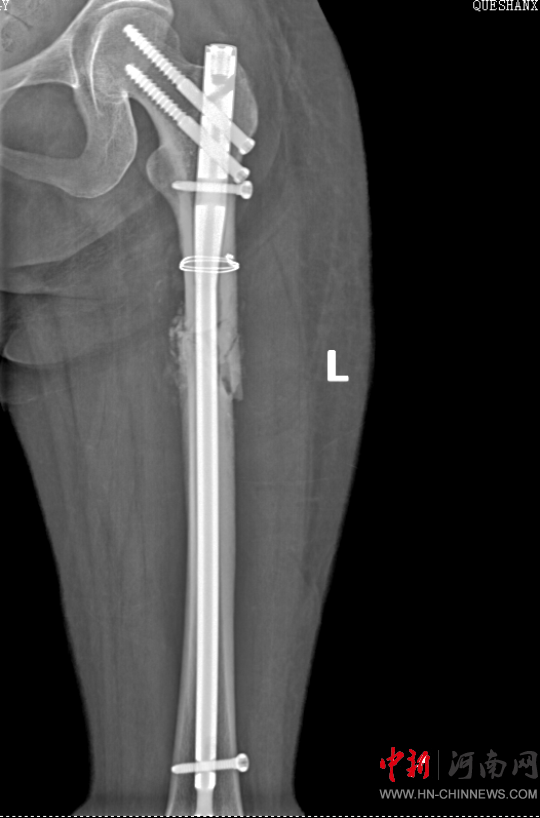

患者病情好轉(zhuǎn)后,該院急診科主任岳春彥和創(chuàng)傷治療團隊為患者制定了詳細的手術(shù)規(guī)劃,傷后第10日,患者在全身麻醉下進行“左股骨粉碎骨折及脛骨粉碎骨折髓內(nèi)釘內(nèi)固定術(shù)+骨移植術(shù)、腓骨骨折復(fù)位內(nèi)固定術(shù)”,病情平穩(wěn)后轉(zhuǎn)入急診科病房治療,切口愈合后,患者轉(zhuǎn)入康復(fù)醫(yī)學(xué)科進行腦功能康復(fù)和下肢關(guān)節(jié)康復(fù)治療。目前,患者能夠與人正常溝通交流,左下肢關(guān)節(jié)功能也恢復(fù)良好,已出院。